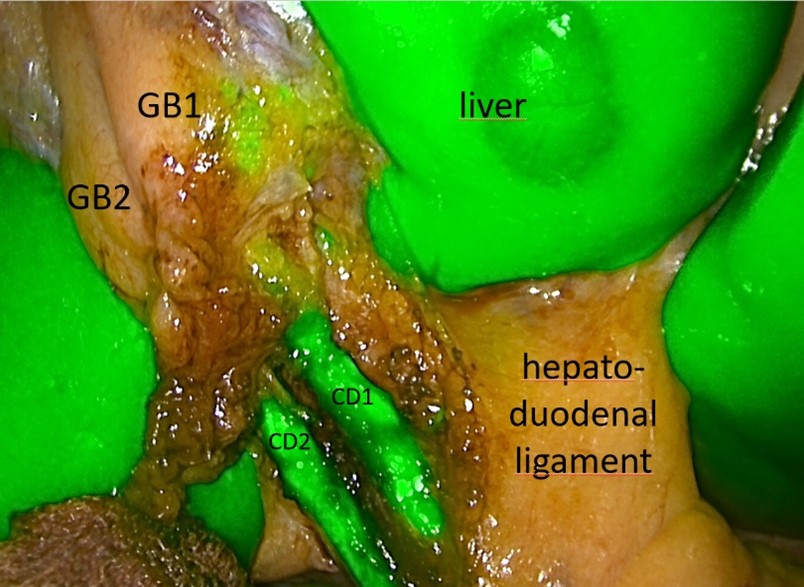

We planned an elective laparoscopic surgery for the removal of both gall bladders, to mitigate the risk of future interventions. The patient received indocyanine green (ICG) 45 minutes before surgery. This enabled intraoperative fluorescence imaging with clear identification of both the cystic ducts, as well as the common bile duct in the surrounding tissue of the Calot triangle. The gall bladders were removed together, the two cystic ducts and the single cystic artery each clipped individually. The patient recovered well and was discharged on the second postoperative day as this is routine in our clinic. Pathohistology confirmed the presence of two gallbladders, with signs of chronic cholecystitis in both.

Figure 2: Intraoperative View of double gallbladder (GB1 and GB2) with separate cystic ducts (CD1 and CD2).

Gallbladder duplication is a rare biliary malformation associated with a higher risk of biliary injuries during cholecystectomy. There are multiple publications describing this difficulty and emphasizing the importance of clarifying the anatomical structures [1,3]. There have been individual reports on the use of ICG for intraoperative imaging of the biliary ducts [4]. Our case clearly confirms that intraoperative fluorescence imaging is a helpful tool to ease intraoperative identification of the biliary anatomy, contributing to better intraoperative decisions and the safety of the procedure.